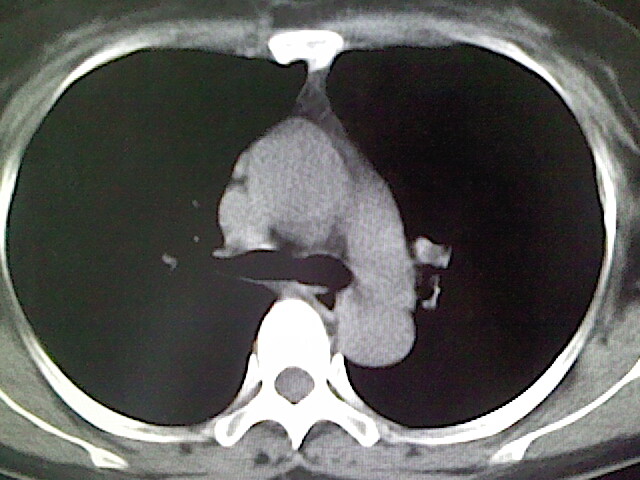

女,52岁,咳嗽,咳痰多日

左下肺陈旧纤维索条!

左肺舌段炎性改变

我见过几例,为炎症后纤维条索

慢性炎症后改变

考虑慢性炎性病灶粘连牵拉改变。

左肺舌叶纤维锁条病变。

左肺上叶下舌段炎症并局部胸膜反应。

左肺舌叶纤维索条影。

左肺舌叶段陈旧性病变

左肺舌段炎性反应。片子的质量太不好了。

左肺舌段炎性

炎性改变

左肺舌叶纤维索条影